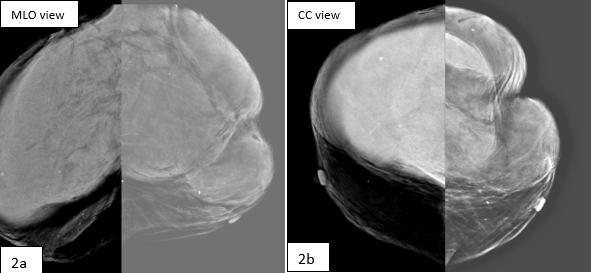

Fig 1a: Ultrasound shows coarse heterogenous liver parenchyma with surface irregularity & nodularity Fig 1b,c,d : CECT Imaging shows Small nodular cirrhotic liver with multi lobulated , well defined masses having mild heterogeneous post-contrast enhancement & few calcific foci in bilateral axilla and inguinal region. Hugely enlarged breasts partly seen in the scan. Ascites present. Fig 2 : 2D mammo (a,b) and Tomo images (c,d) of both breasts show bilateral high density large masses with smooth margins and no architectural distortion however few course heterogenous calcifications present randomly in breast parenchyma. (compromised scan quality is attributed to massive breast size) Fig 3 a,b,c,d : Ultrasound of bilateral breasts show iso to heteroechoic large breast masses occupying almost entire breasts. Normal breast tissue was compressed and difficult to identify. Colour doppler demonstrates significant vascularity within the masses. Fig 4 : Ultrasound of axillary lymph nodes. Fig 5 a,b : Biopsy from breast masses showed amyloid deposits (pink) predominantly around the ducts and blood vessels (a), demonstrated well on congo red stain (b).